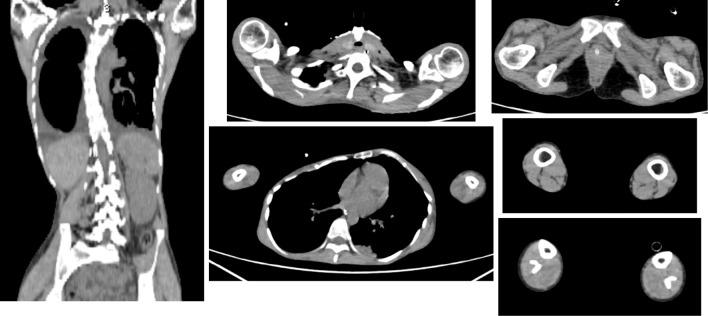

Nemaline myopathy (NM) is a rare muscle disease with various clinical types. In some cases, NM can lead to type 2 respiratory failure and right heart failure. We herein report a patient with congenital NM with nebulin gene mutation who presented with acute right heart failure and type 2 respiratory failure due to respiratory muscle paralysis after upper respiratory tract infection, needing a permanent ventilator for assistance. However, the limb and trunk muscle strengths were within normal limits. This case showed that NM should be considered as a cause of right heart failure and type 2 respiratory failure.

肌强直性营养不良(NM)是一种罕见的肌肉疾病,具有多种临床类型。在某些情况下,NM 可导致 2 型呼吸衰竭和右心衰竭。本研究报告了 1 例先天性 NM 合并 nebulin 基因突变的患者,该患者因上呼吸道感染后呼吸肌麻痹而出现急性右心衰竭和 2 型呼吸衰竭,需要永久性呼吸机辅助。然而,四肢和躯干肌肉力量均在正常范围内。该病例表明 NM 应被视为右心衰竭和 2 型呼吸衰竭的病因之一。